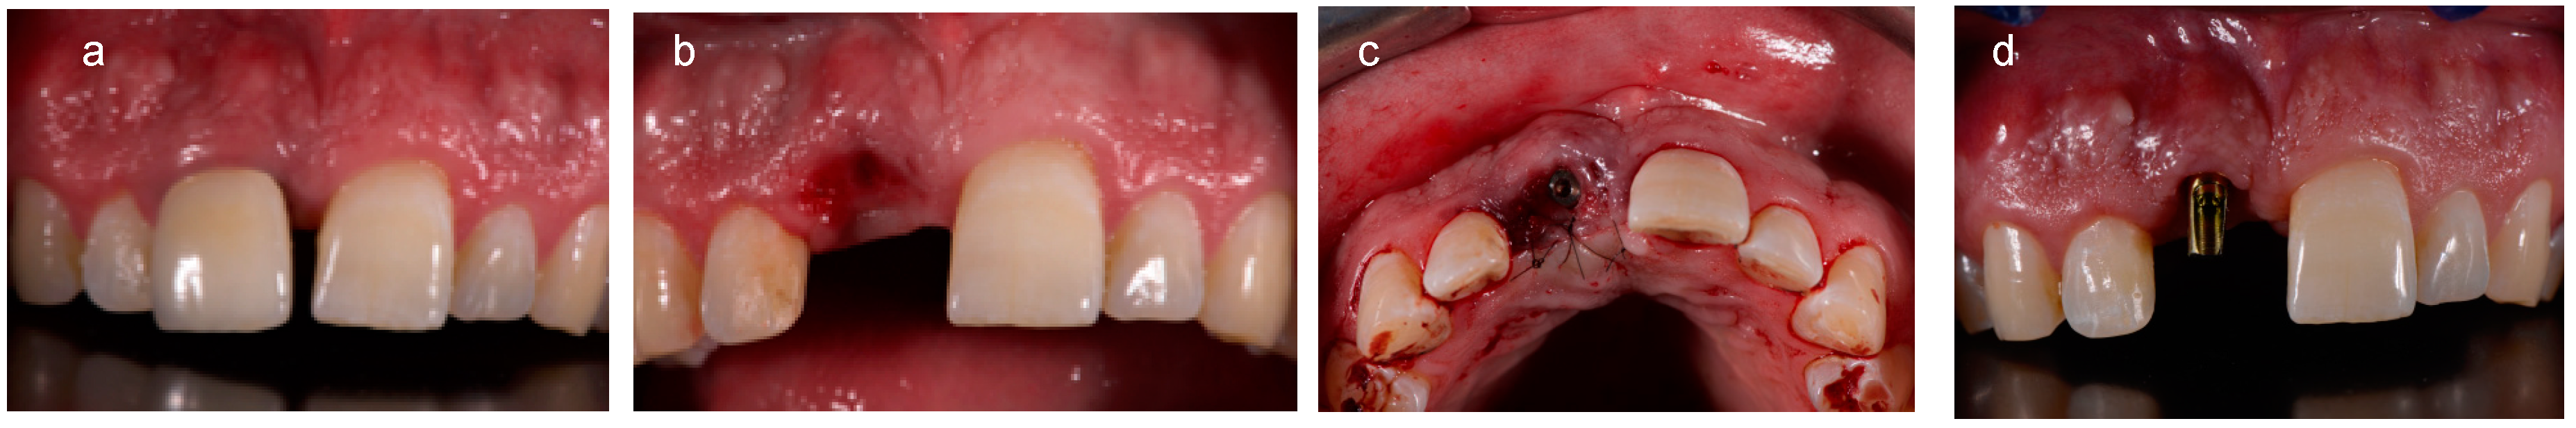

2.2. Analogic Work-Flow